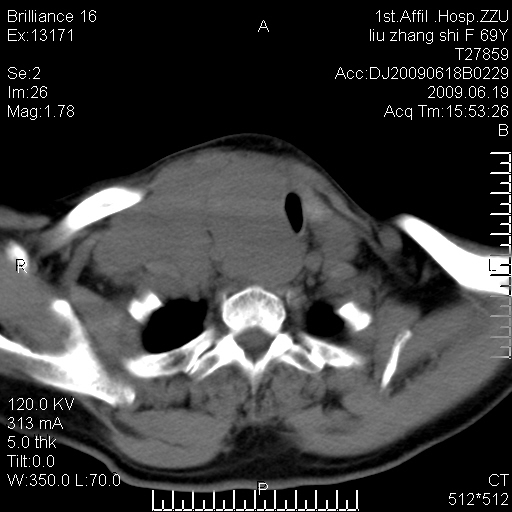

标题: CT26782:女,69岁,颈部占位,3天后公布病理结果。

【病理证实系列】女,69岁,颈部占位,有病理结果,3天后公布。(由于病例时间较久,临床资料不全,请网友见谅)本系列将有几百种常见、少见及罕见病例,均经病理证实。病例资料来自郑州大学第一附属医院。与网友共享,本人有空就发。

甲状腺癌并颈部淋巴结转移。感谢楼主的良苦用心,谢谢。

甲状腺癌并颈部淋巴结转移。

需与鼻咽癌鉴别!

支持甲状腺癌广泛侵及周围结构并颈部淋巴结转移。

鉴别:淋巴瘤、恶性神经源性病变、恶性纤维组织细胞瘤。

病理结果:颈部非霍奇金淋巴瘤。